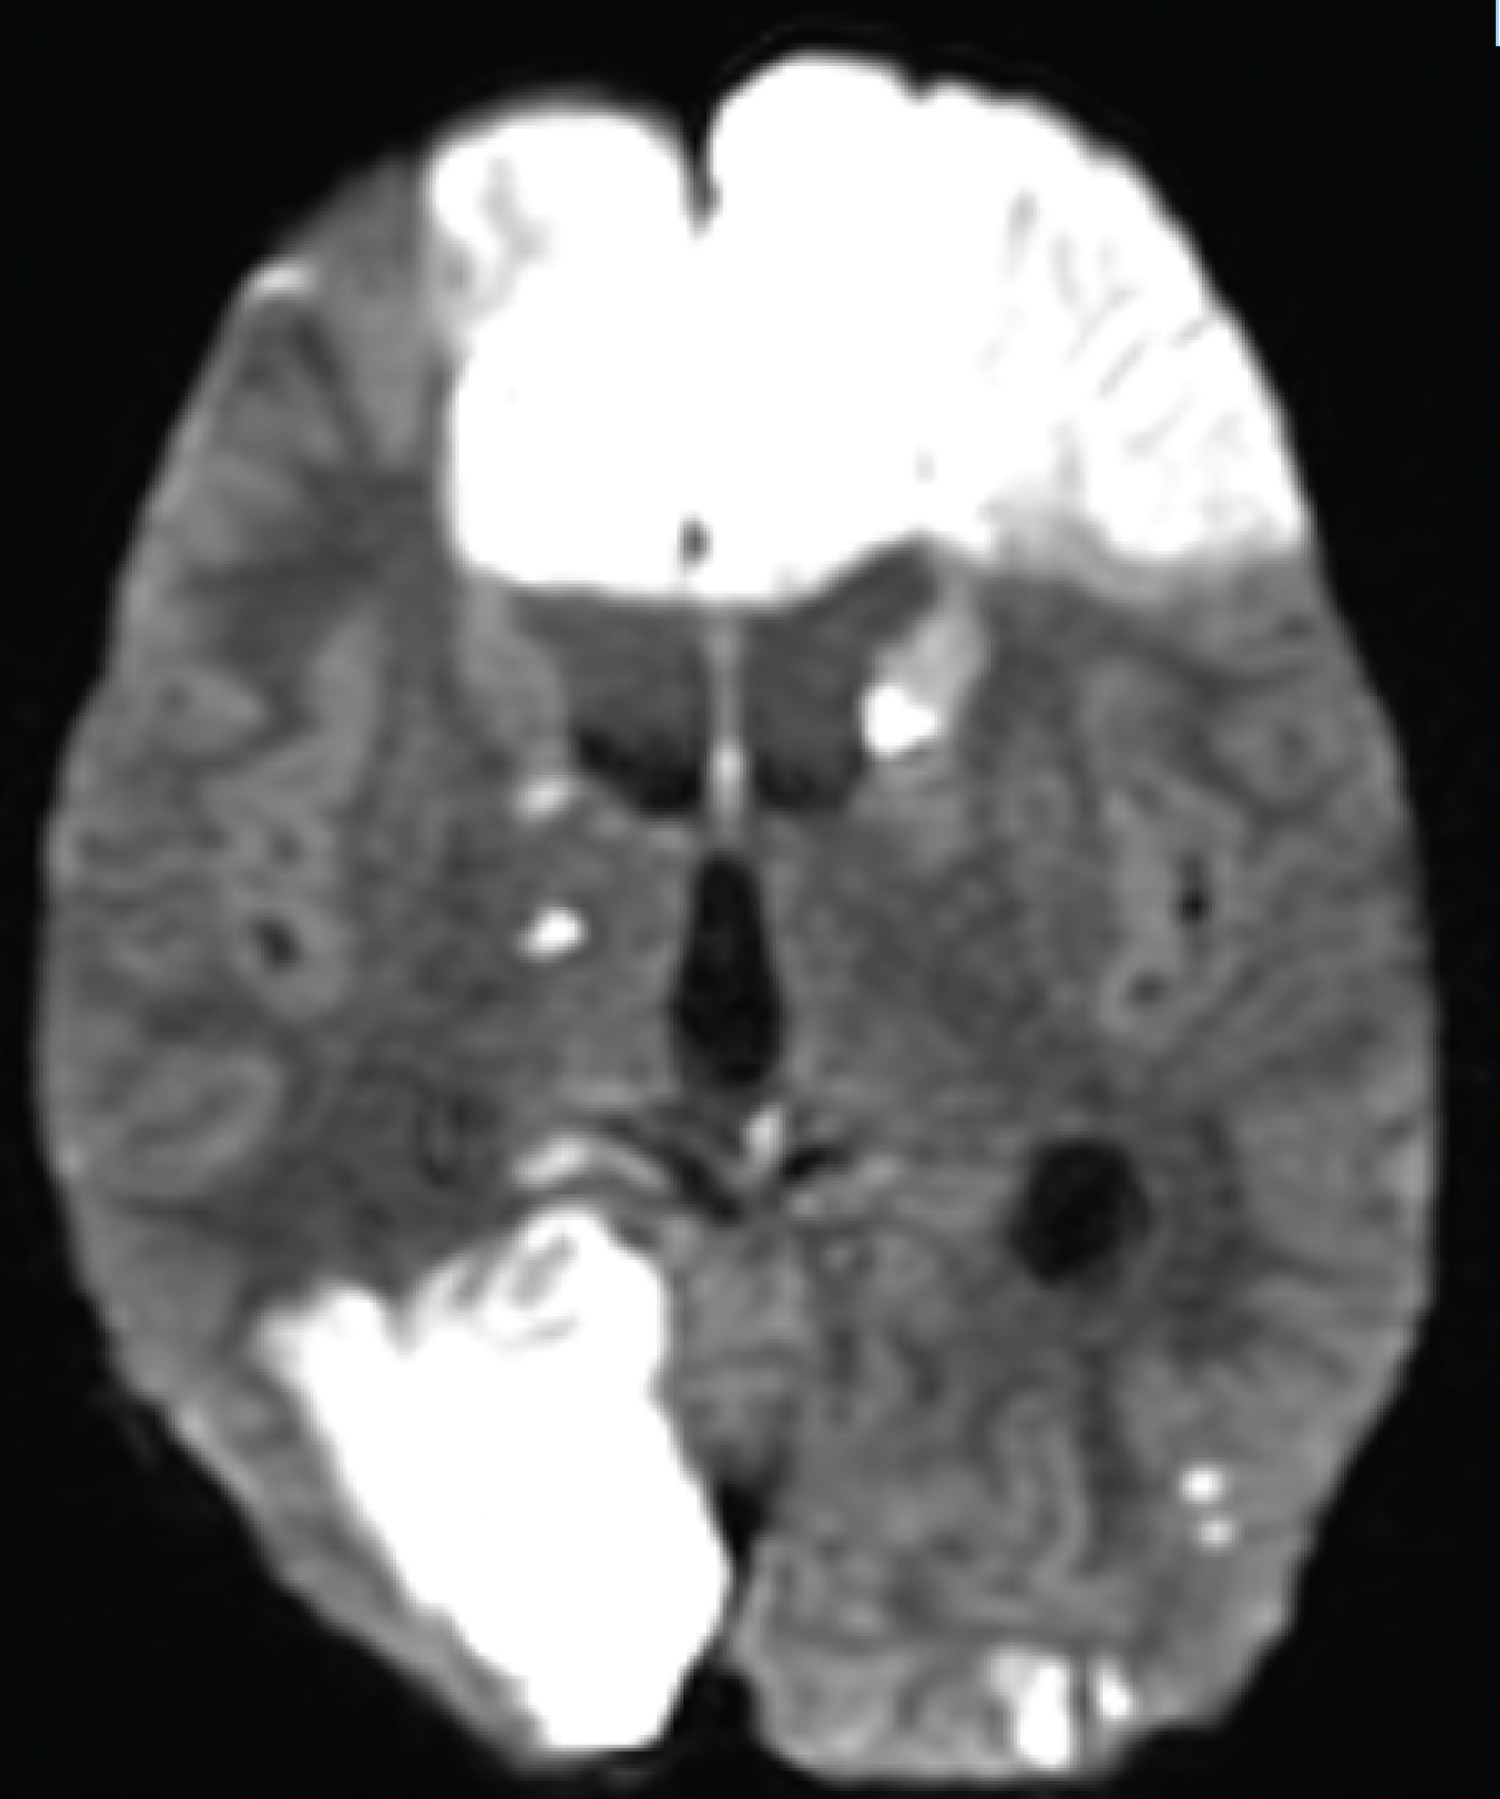

The patient is a 2-year-old child who referred to the pediatric emergency room due to loss of consciousness and suspected seizure symptoms. Also, the child's COVID-PCR test was reported positive 12 days before the visit, and the child had symptoms of cough and mild fever at the same time, which recovered at the same time. At the time of visit, the child was sleepy. He opened his eyes with painful stimulation and moved his right limbs less. Pupils were mid-sized, reactive and symmetrical. In the following examinations, there was no deviation in the eyes. Gag and corneal reflexes were normal. The child had spontaneous breathing and blood pressure and heart rate were normal. In the continuation of the history of the child, intolerance to food and milk was also mentioned. The initial blood sugar of the child was normal. After performing the initial measures, due to the unavailability of MRI, the child was subjected to brain CT scan. In the initial CT scan, the large size of the cerebral ventricles and hydrocephalus were mentioned for the child (Figure 1, Figure 2, Figure 3, Figure 4, Figure 5 and Figure 6). Due to hydrocephalus and clinical signs of increased ICP, the child was urgently transferred to the operating room, and while measuring ICP and sending a CSF sample, a ventriculoperitoneal shunt was implanted for the child. The child's icp was measured at 32 cmH2O. After the surgery, the child's level of consciousness improved relatively. The variables of the CSF sample sent were all in the normal range. The next day, the child underwent brain MRI and MRA. In the performed MRI, a clear signal change was seen in the frontal and occipital lobes, which is shown in photos No. 2, 3, 4, 5 and 6. According to the MRI, a biopsy was taken from the child's right frontal lobe for a definitive diagnosis. Immunohistochemical examination revealed the demyelinating nature of the specimen, in which extensive infiltration of basal macrophages and activated microglial cells was seen, while axons were largely preserved. No sign of vasculitis was seen in the examination of the sample. In this way, the result of the examination of the brain sample confirmed ADEM. With this diagnosis, the child was treated with corticosteroids and IVIG. The disease responded dramatically to the treatment. All the child's symptoms improved within two days and the child's level of consciousness reached its normal range. Finally, the child was discharged from the hospital after a week with a good general condition.

Figure 3: ADC image shows signal changes in the frontal and occipital lobes. View Figure 3